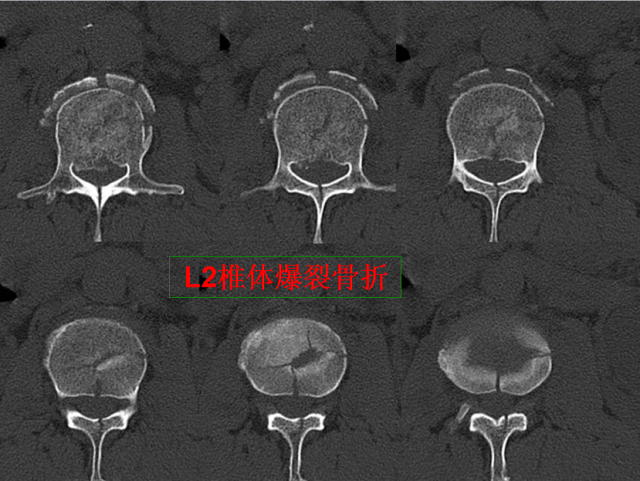

骨折篇

01

定义:骨折{Fracture}是指骨的完整性和连续性的折裂或粉碎。包括创伤性骨折、疲劳性骨折和病例理性骨折。 临床上以创伤性骨折*常见。